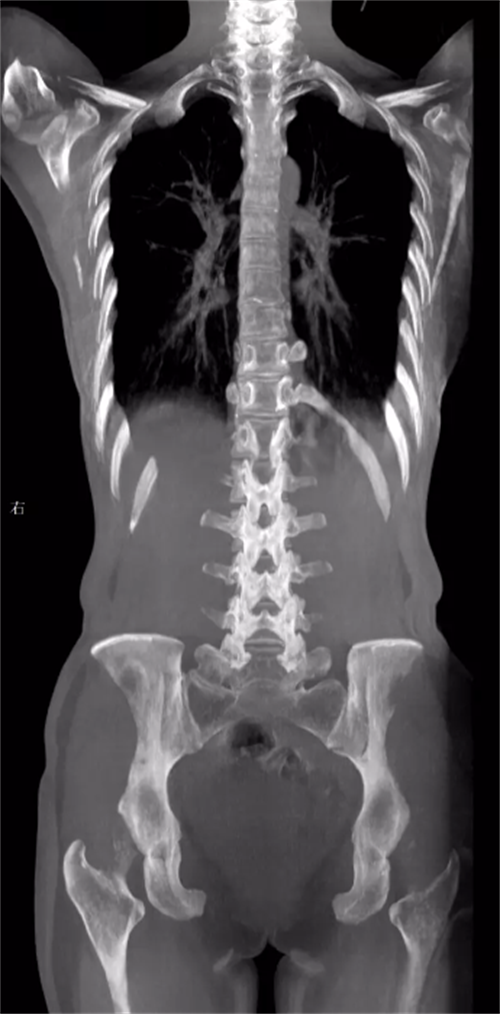

②三维化。三维是在动态的基础上实现的。那么为什么要将动态DR往三维化方向发展呢?原因就是目前常规动态DR在临床上有一定临床应用局限性。传统二维平片它极易受到投照角度以及摆位的影响导致漏诊和误诊,而三维检查能全面的呈现被检查部位在多个角度下的三维影像信息,能够提供精准且直观量化的测量数据辅助临床做出精准诊疗。(三维扫描重建图像)

当然会有人问为什么三维检查不在CT和MRI上进行呢。据研究表明,人体在卧位和立位状态下脊柱、关节的形态会发生改变,那么在仰卧位状态下拍摄的临床影像就难以反映人体正常承重状态下的骨骼关节信息,所以也有临床应用局限性。

在三维化研究的方向上,目前这几个厂家的技术算业界领先。首先就是安健科技国内首创的WR-3D,实现负重位下三维扫描与重建。WR-3D是通过CBCT原理来实现的,通过创新型的非等中心扫描实现业内最大FOV,解决业内其他厂家无法实现的一次扫描就可包含双侧髋关节、双下肢等的弊端。其次就是法国EOS,当然它实现三维扫描的原理与安健大不相同,它是通过两组垂直放置的探测器自上而下扫描,获得正侧位的影像,在通过正侧位影像来做模板匹配,拟合出三维影像。最后就是涛影,它的原理类似于G型臂,通过双平面系统扫描,将双平面影像导入骨与关节三维分析工作站,获得三维图像。不过值得一提的是,这三个厂家目前只有安健科技的WR-3D是真三维扫描。(左边图像为安健科技WR-3D,右边图像为法国EOS)

总的来说三维摄影不仅具备动态DR的全部功能,且较动态DR的二维扫描,三维摄影能够提供更加优质的临床图像以及精准的骨关节参数信息,同时可以补位CT和MRI,实现CT和MRI无法满足的负重位下三维扫描与重建,同时相较于CT,且三维DR还具有比CT剂量更低的优势。